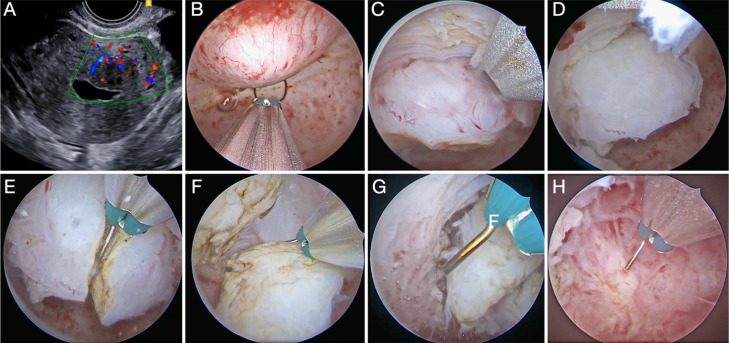

Abstract Image